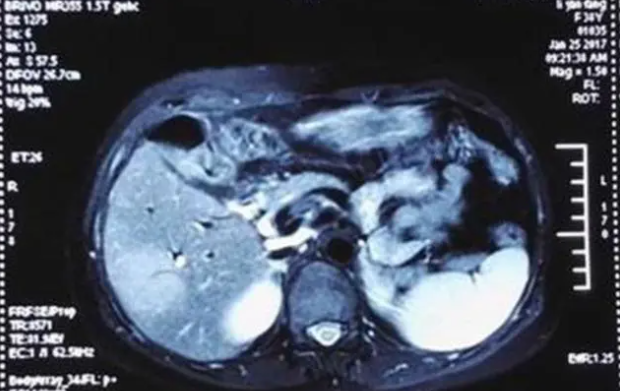

9月6号,阿珂孕21周,麒麟瓜一般的子宫和胎儿,与“番薯”一般的肿瘤做邻居,大大增加了手术难度。在胃肠外科、产科和麻醉科保驾护航下,阿珂接受了“右半结肠癌根治术”。手术过程平稳且顺利。